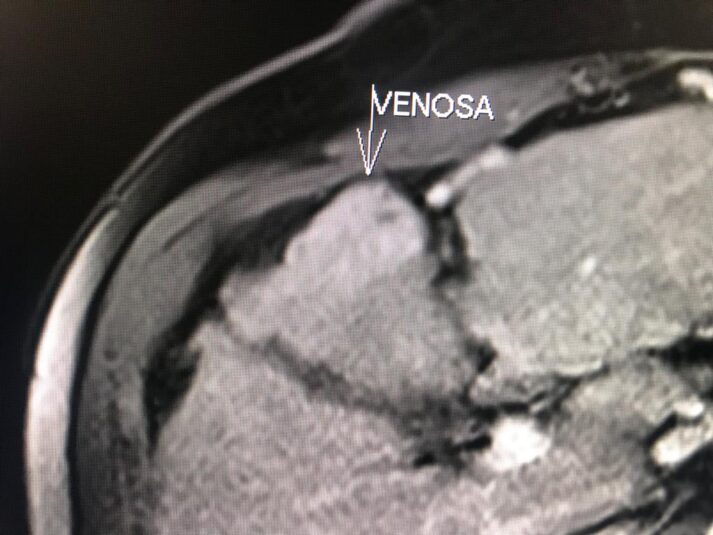

En el presente caso, encontramos una lesión típica de hepatocarcinoma en el segmento 5 ( hiperintensa en T2, restringe en la Difusión con ADC bajo. Realza heterogéneamente postcontraste EV, con wash out y presencia cápsula tardía).